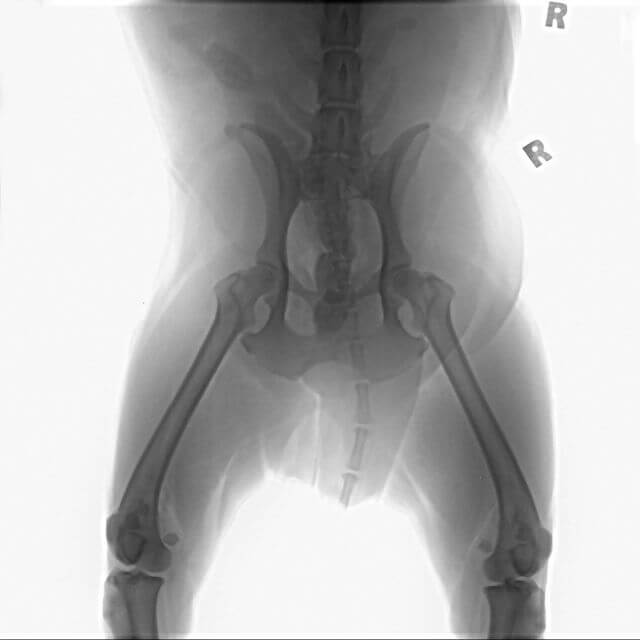

Dog pelvic xrayAt Animal Hospital In Fairfield, we offer x-rays. If ultrasound or advanced imaging is recommended for your pet, we will refer you to a trusted specialist. If a specialist’s opinion is needed, we can send radiographs electronically to a group of radiology specialists in Sacramento. They will read the images for us and provide their expert opinion within 24 hours. Ultrasounds require a specialist which can typically be scheduled within 1-2 business days.